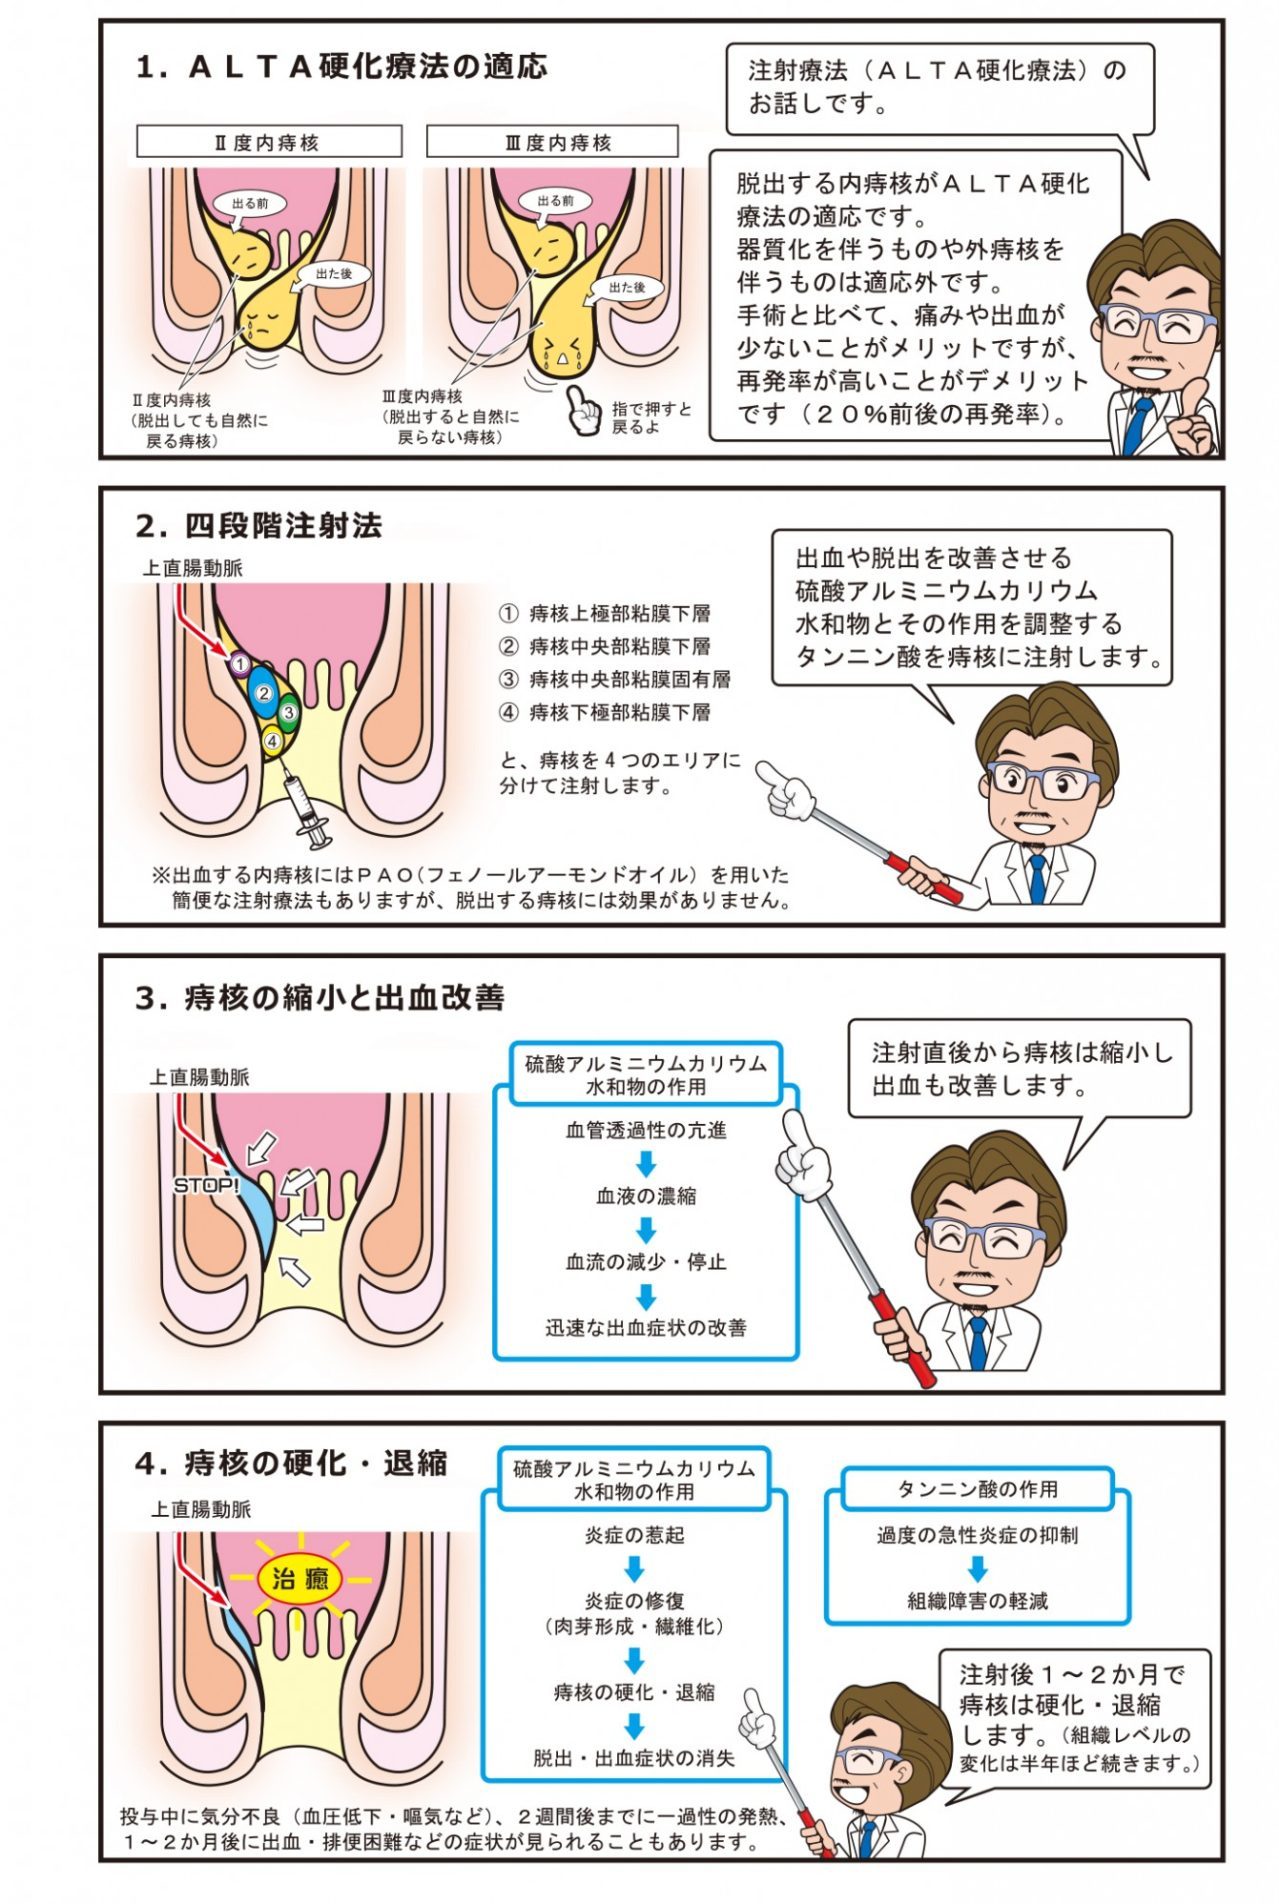

マンガで分かる痛くない大腸内視鏡検査と切らない痔の治療神戸市三宮の大腸内視鏡なら「みつみや大腸肛門クリニック」。